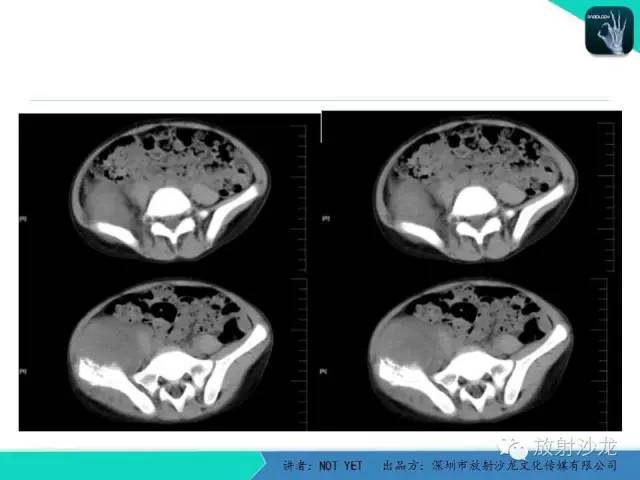

【病例】右侧髂骨Ewing肉瘤1例CT影像表现